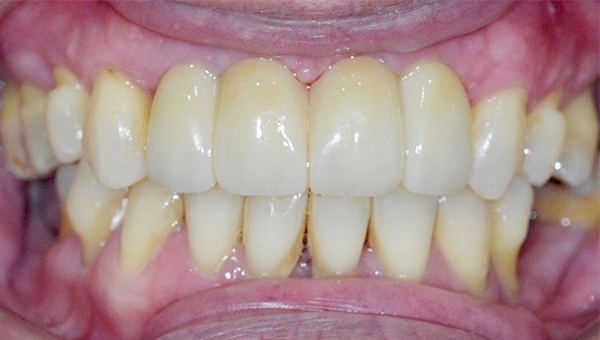

치료사례임플란트

강*란 임플란트 시술 사례

전체 임플란트

2025.02.07

치료 전

2025.08.19

치료 후